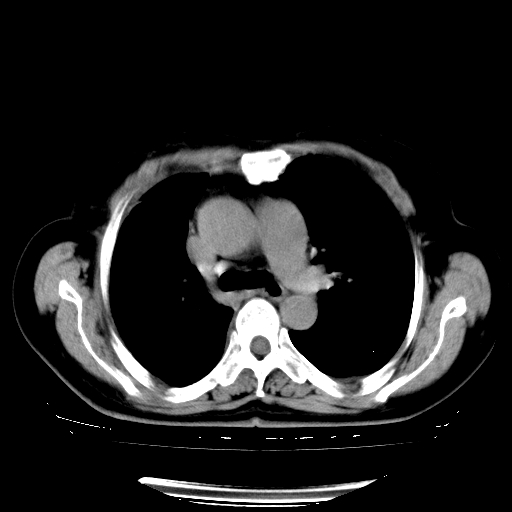

以下是引用zhangzhongshou在2008-3-22 12:52:00的发言:[br]1、右侧液气胸。[br]2、腹水。建议进一步检查。

以下是引用鲁巨ct在2008-3-22 14:10:00的发言:[br]1、右侧液气胸,右中下叶节段性不张。[br]2、腹水,建议上腹部ct检查

以下是引用zjzjr在2008-3-22 17:19:00的发言:[br]1、右侧液气胸,右下叶节段性不张。[br]2、腹水,建议上腹部ct检查